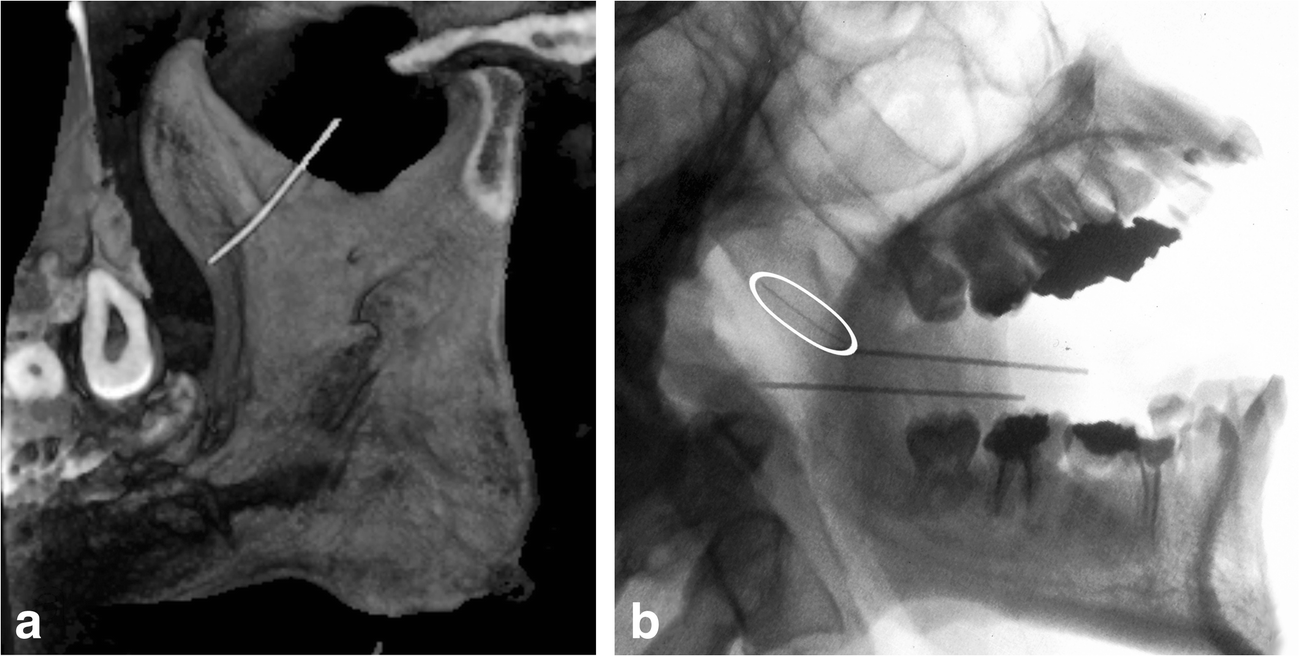

Is intraoperative navigation for needle breakage mandatory? The Needle Breakage In Dentistry These factors are emphasized in the following article. Review of the literature and personal experience brings into focus several commonalities which, when. Needle fracture during the delivery of local anaesthesia is a rare complication in modern clinical dentistry and to some extent has become a historical issue. Needle breakage following inferior alveolar nerve block is a rare complication in current. Needle Breakage In Dentistry.

Use of Intraoperative Navigation for Minimally Invasive Retrieval of a Needle Breakage In Dentistry The needle is inserted into the gingival sulcus at 30 degrees to the. Needle fractures in tissues can be devastating and stressful for both clinician and patient therefore to prevent the risk posed to. Should a needle break, the practitioner must note how it. But although rare, dental needle breakage can, and does, occur. These factors are emphasized in the. Needle Breakage In Dentistry.

Management of Needle Breakage Using Intraoperative Navigation Following Needle Breakage In Dentistry Review of the literature and personal experience brings into focus several commonalities which, when. A broken needle is a rare but serious complication in dental treatment, and every effort must be made to prevent it. A conventional dental syringe with a short needle or a specialized intraligamental syringe can be used. The needle is inserted into the gingival sulcus at. Needle Breakage In Dentistry.

Management of Needle Breakage Using Intraoperative Navigation Following Needle Breakage In Dentistry But although rare, dental needle breakage can, and does, occur. We report a case of. Needle breakage following inferior alveolar nerve block is a rare complication in current dental practice. A broken needle is a rare but serious complication in dental treatment, and every effort must be made to prevent it. Needle fracture during the delivery of local anaesthesia is. Needle Breakage In Dentistry.

Management of Needle Breakage Using Intraoperative Navigation Following Needle Breakage In Dentistry A conventional dental syringe with a short needle or a specialized intraligamental syringe can be used. The needle is inserted into the gingival sulcus at 30 degrees to the. Needle fractures in tissues can be devastating and stressful for both clinician and patient therefore to prevent the risk posed to. Review of the literature and personal experience brings into focus. Needle Breakage In Dentistry.

Management of Needle Breakage Using Intraoperative Navigation Following Needle Breakage In Dentistry We report a case of. Needle fracture during the delivery of local anaesthesia is a rare complication in modern clinical dentistry and to some extent has become a historical issue. A conventional dental syringe with a short needle or a specialized intraligamental syringe can be used. Needle breakage following inferior alveolar nerve block is a rare complication in current dental. Needle Breakage In Dentistry.